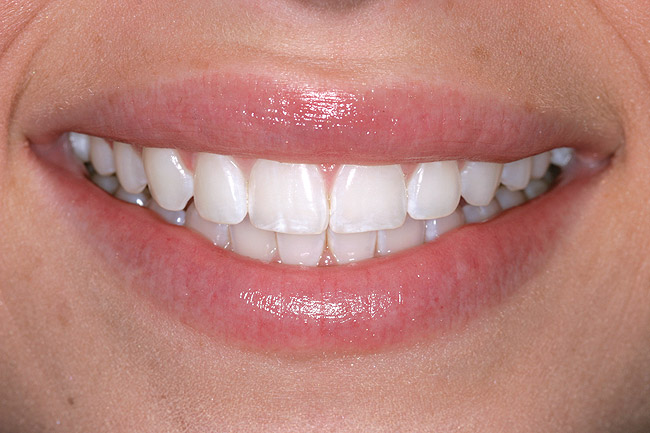

Figure 12 through Figure 14 Final restoration of the severe wear case seen in Figure 9 through Figure 11. The incisal edge position was maintained.

Figure 13

Figure 14

This author has found that a good starting point for the central incisor length is 10.5 mm. The “E” and rest positions are then used to determine the approximate vertical position to place the incisal edge. In many cases involving tooth wear, the patient will want longer-looking teeth. Simply adding length to the incisal to achieve 10.5 mm will often result in encroachment on the envelope of function and the neutral zone. Phonetically, the position of the incisal edge is important when considering the lower lip. The lower lip must interact with the incisal edge in a natural, effortless fashion. This is evident during the pronunciation of words beginning in the letters “V” and “F” (Figure 8). The incisal edge contact should occur in the moist or inner vermilion border of the lip and not the cutaneous or dry portion. This error can often been seen in restorations that are too long incisally.6 The patient in Figure 9 has obviously been occlusally compromised and has extreme wear. However, consider the patient’s current incisal edge location seen in the “E” position (Figure 10). The current position is very close to the ideal vertical position. If an ideal incisor length is to be achieved, the length must be captured from the apical direction. This particular case is an example of passive delayed eruption. As the teeth slowly wear, the alveolar process migrates to keep pace with the tooth loss. The cementoenamel junction, soft tissue attachments, and incisal edge position stay anatomically in place as the process migrates.11 The final restorative process for this patient included hard tissue crown lengthening to recapture added tooth length (Figure 11) and maintenance of the current incisal edge position. The proper maxillary occlusal plane, envelope of function, and anterior guidance were then restored. All of the above parameters were established in the diagnostic phase and then tested in long-term provisionals. The final restorative result can be seen in Figure 12 through Figure 14.